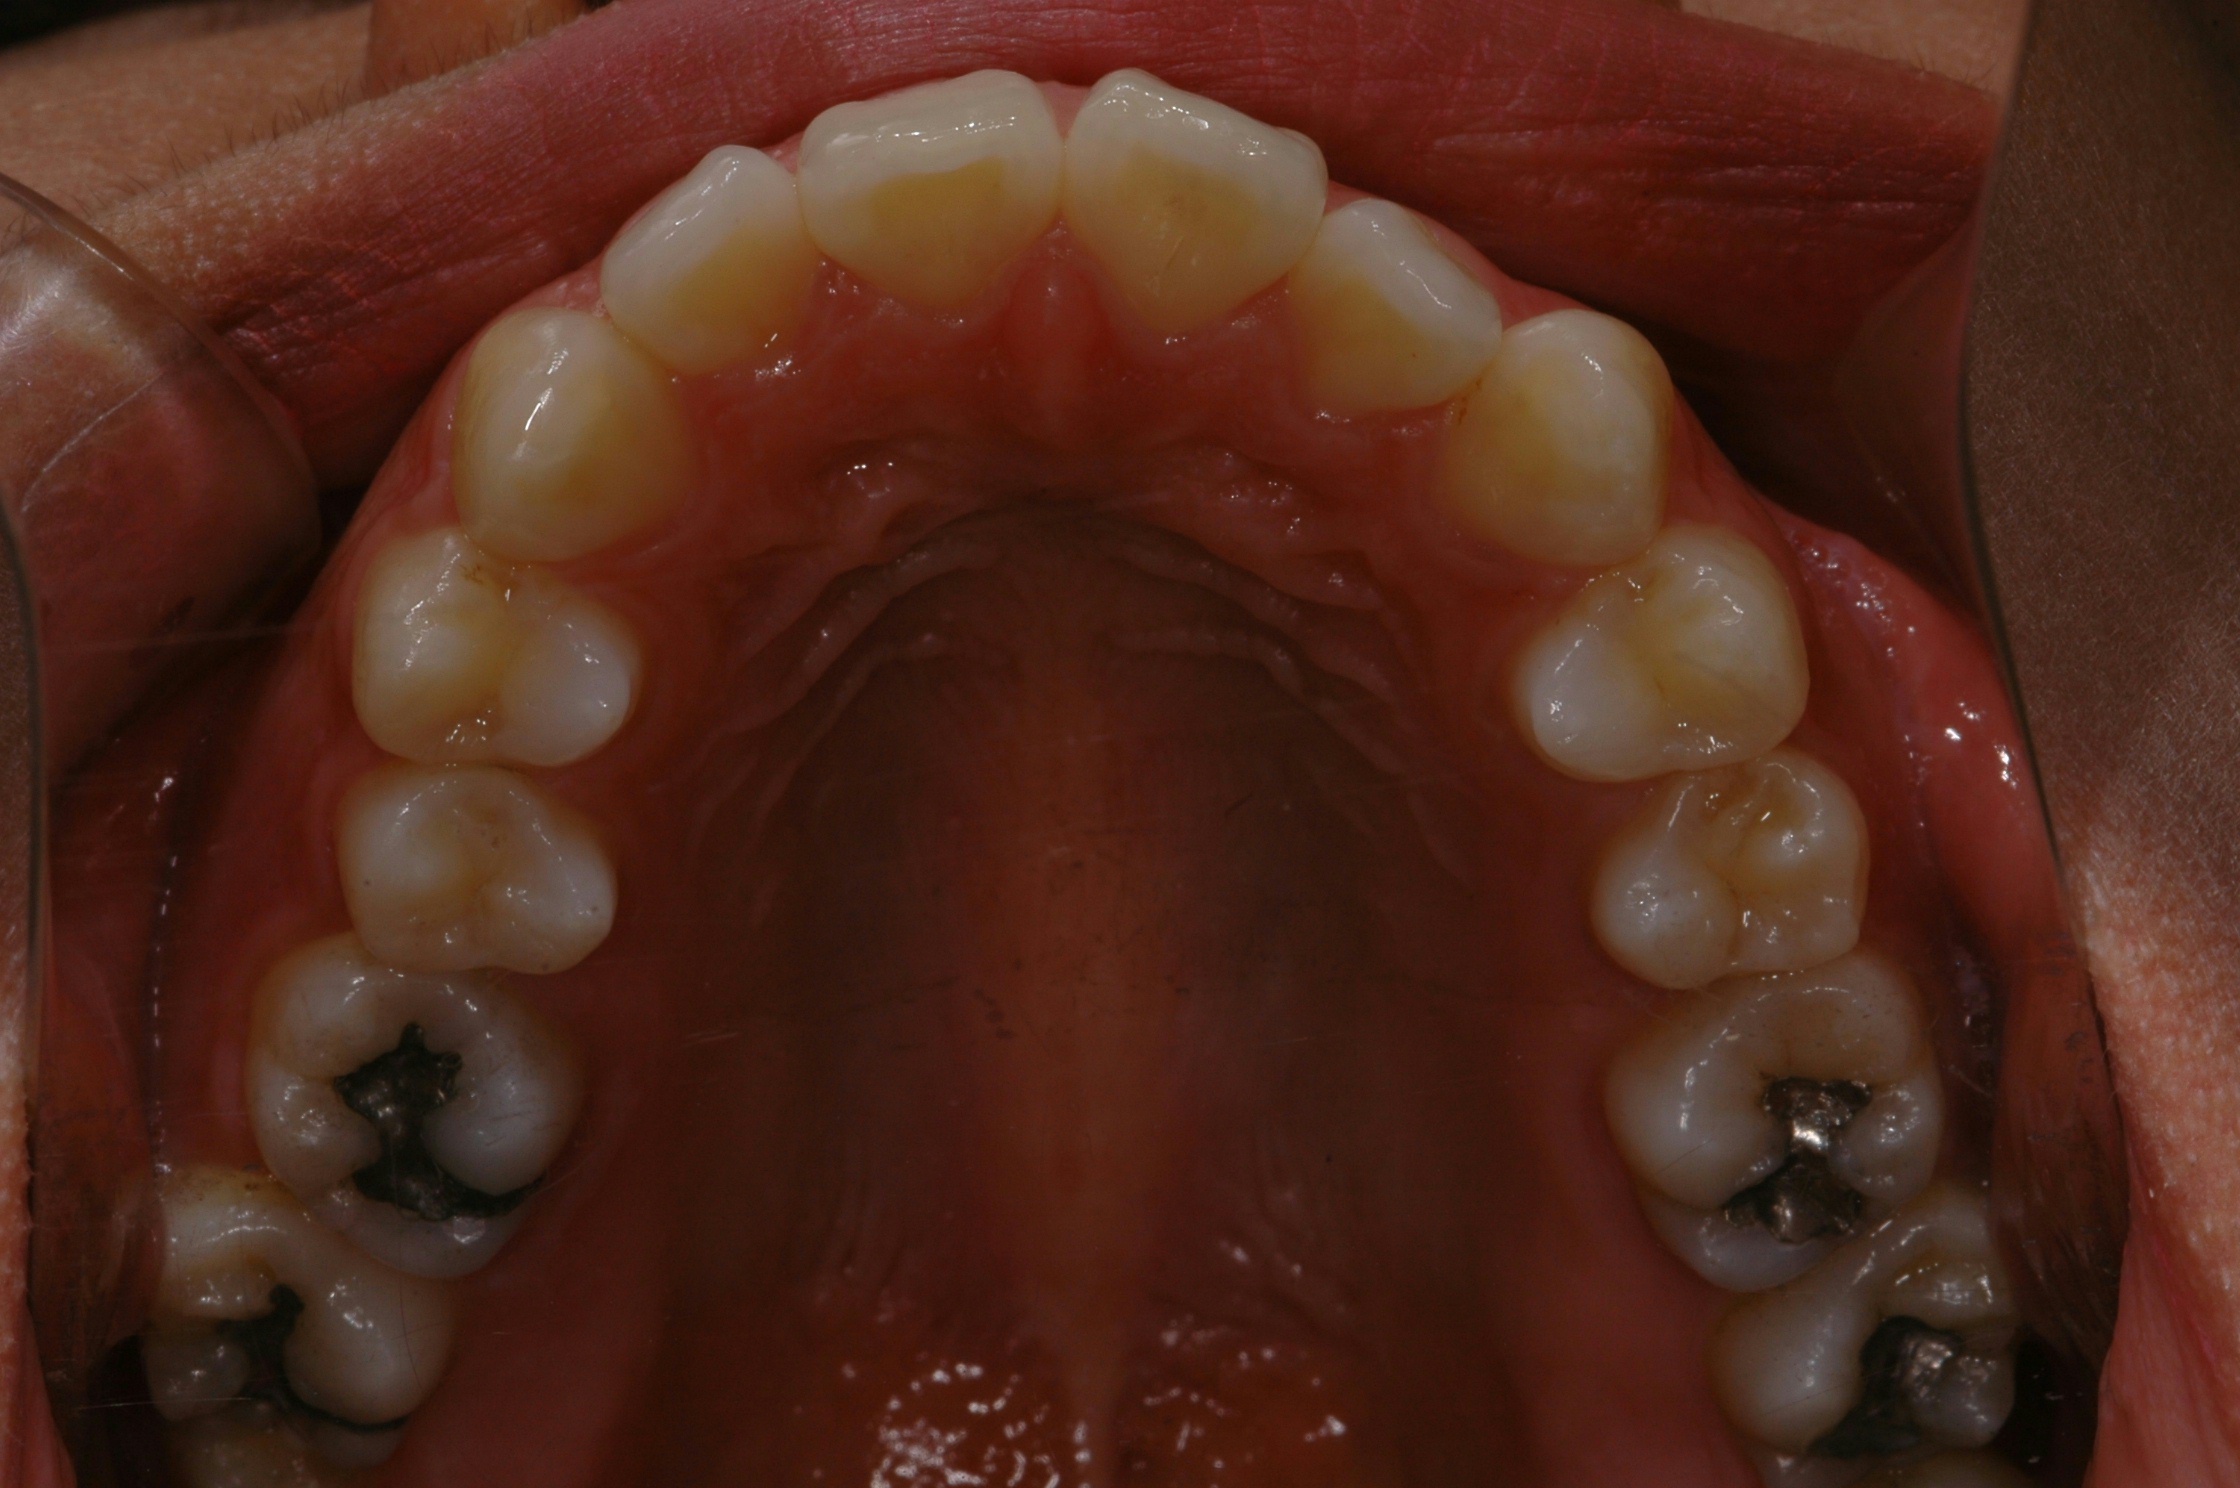

치료 전 사진입니다.